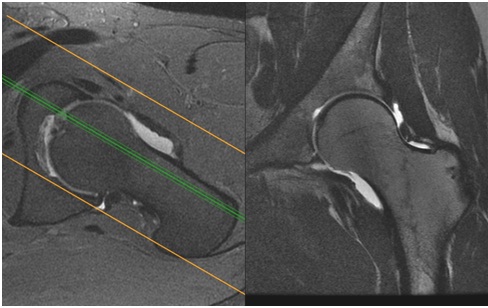

Resonancia convencional. En este ejemplo podemos observar las ventajas del líquido intra-articular en la evaluación intra-articular.

Artroresonancia de cadera